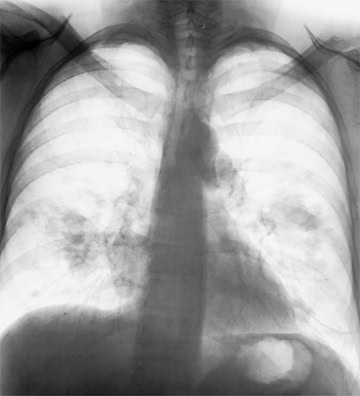

Değişebilir Renk ve Tek Renk Görüntü

ASUS HealthCare ekranlar, farklı derinliklerden röntgen okumaya yardımcı olmak için pozitif ve negatif film moduna sahip renkli ve tek renkli kullanım modları sunar.

Kapalı (Normal, Renk)

Pozitif Film (Tek Renk)

Negatif Film (Tek Renk)